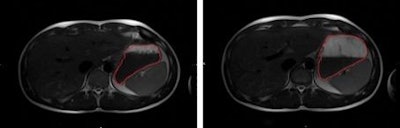

The MRI scans showed that drinking the large glass of water doubled the stomach content compared to the smaller glass. In addition, subjects reported feeling fuller and less hungry after drinking the larger amount of water. Lead author Guido Camps and colleagues also found that brain activation increased with greater distention of the stomach.

Above, MRI shows a subject with the small volume of water (left) and the larger volume (right), delineated in red. Below, brain scans showed that activation in the insula increased when the stomach was more distended. Image credit: G Camps, R Veit, M Mars, C De Graaf, P Smeets.This new approach of obtaining information simultaneously on the brain, stomach, and subject-reported feelings could lead to new insights; for example, brain activation in the midtemporal gyrus appeared to be influenced by the increase in water, according to the Society for the Study of Ingestive Behavior (SSIB).